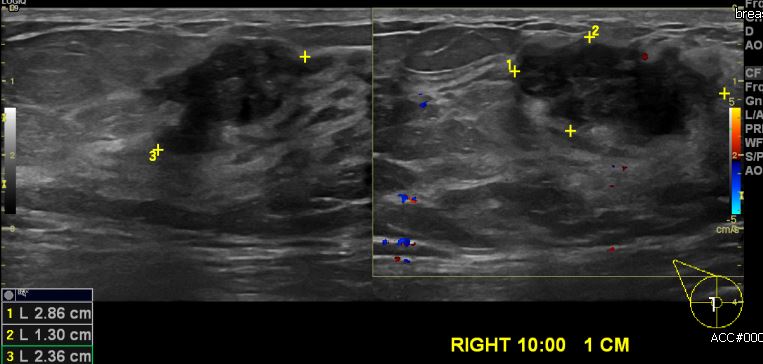

우측 만져지는 멍우리로 내원하신 40대 여성분으로 본원 유방초음파 시행 후

우측 10시 방향 1cm  떨어진 거리에 만져지는 혹 중심핵생검 시행하여 우측 침윤성

유관암 진단 되었습니다.